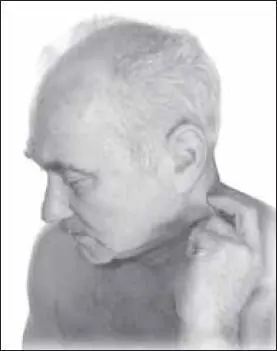

Завершить процедуру надо разминанием грудинно-ключично-сосцевидной мышцы с помощью щипцеобразного приема (рис. 121).